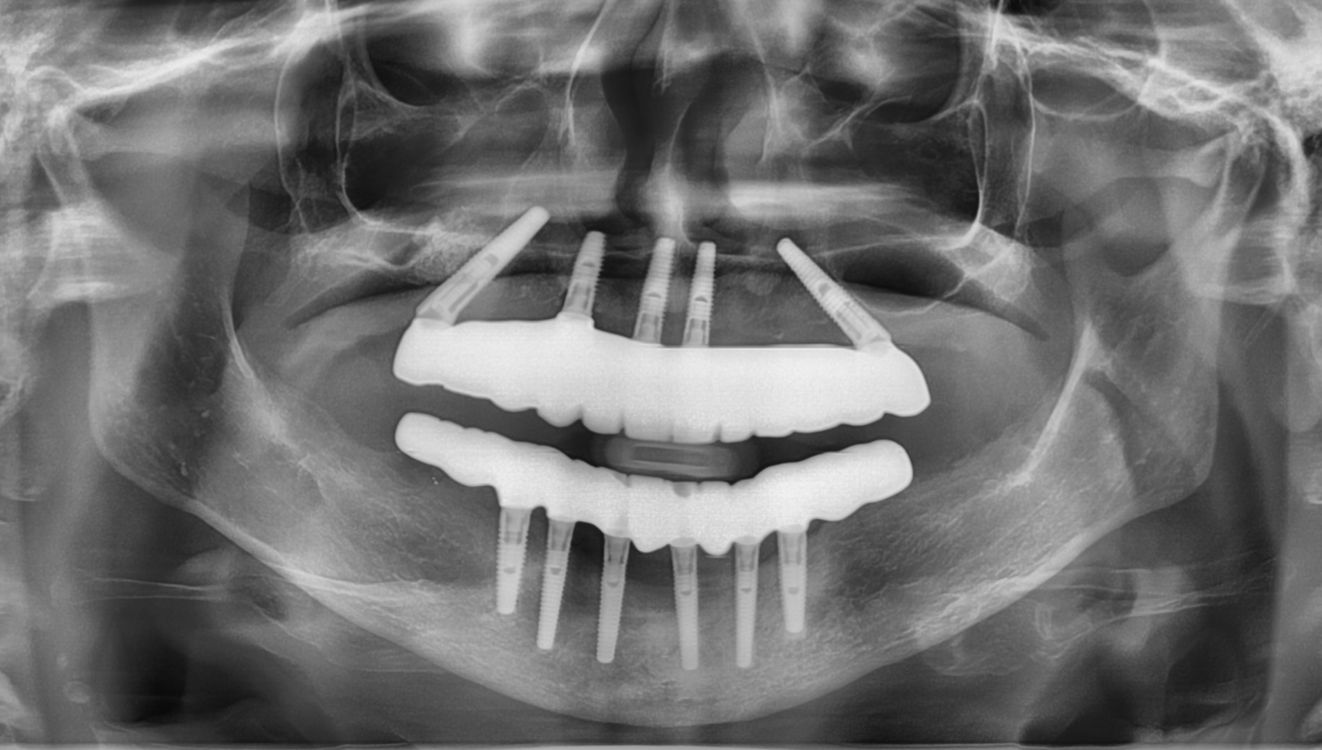

The answer is a resounding YES! It’s technically possible, but it’s also very easy to be exposed by radiographs or a CT scan. Doing so would have put that spy dentist at great risk. I would not wanna be that person.